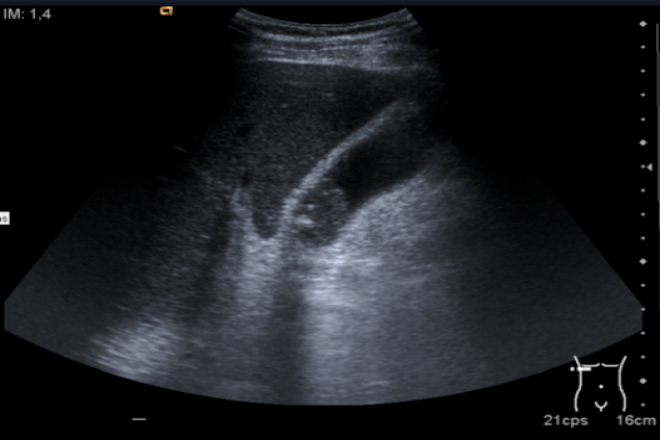

Pruebas de imagen

El ultrasonido abdominal es la prueba más útil para diagnosticar litiasis vesicular, detectando cálculos mayores de 3mm, independientemente de su opacidad. En la imagen, los cálculos aparecen como áreas hipoecoicas que se desplazan con el movimiento del paciente.